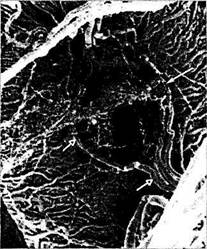

Рис. 3.7.19. Особенности кровоснабжения зрительного нерва (по Hayreh, 1963):

1 — мягкая мозговая оболочка, окутывающая сосуды; 2 — воз­вратные короткие задние ресничные артерии и пиальные сосуды; 3 — возникающие из пиальных артерий артериолы; 4 — интра-нейральные ветви центральной артерии сетчатки; 5 — склераль­ная часть короткой задней ресничной артерии; б — ветвь задней короткой цилиарной артерии, проникающей в нерв; 7 — добавоч­ный хориоидальный сосуд, проникающий в зрительный нерв; 8 —глазная артерия; 9—центральная артерия сетчатки; 10 — сосудистый круг Цинна—Халлера; //—задняя длинная реснич­ная артерия; 12 —твердая мозговая оболочка; 13 —паутинная оболочка; 14 — мягкая мозговая оболочка; 15 — решетчатая пла­стинка; 16 —сетчатка; 17 —сосудистая оболочка; 18 — склера